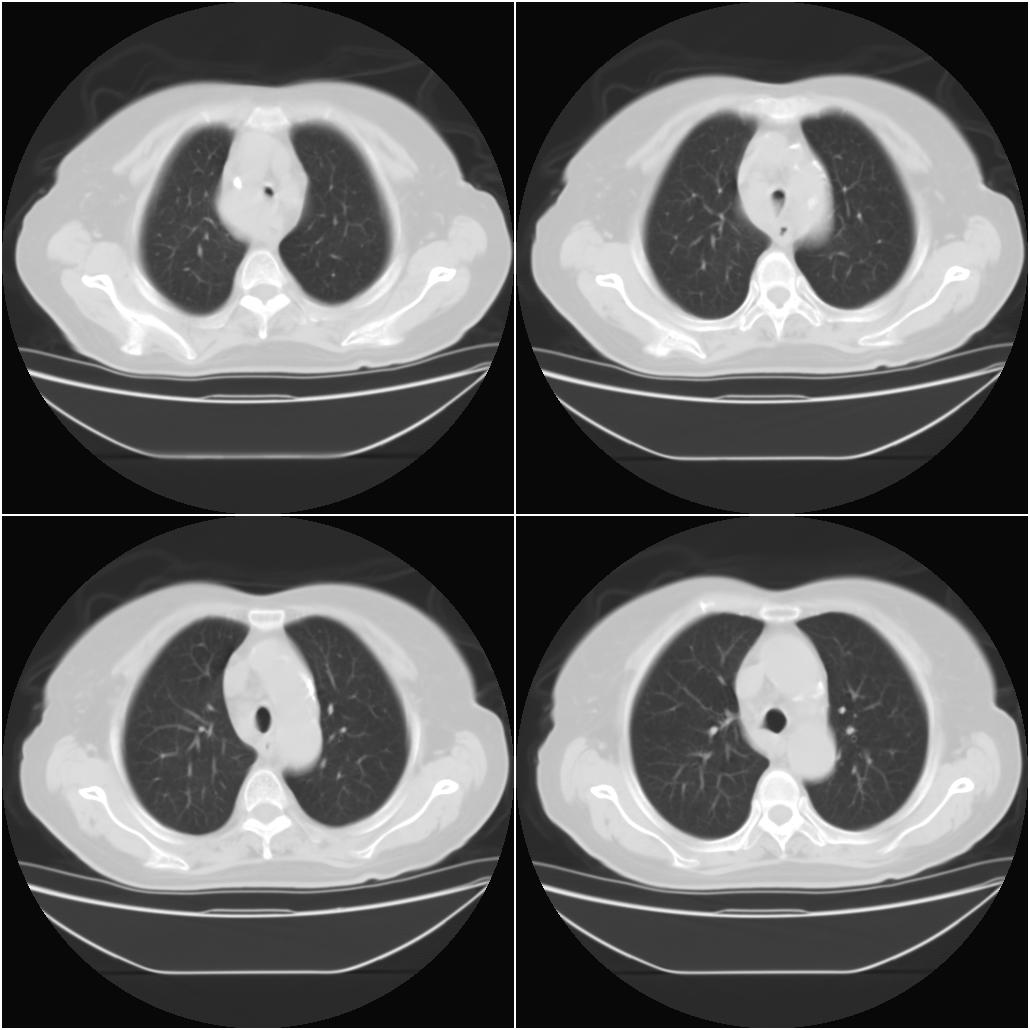

以下是引用sxlcbc在2007-12-23 4:27:00的发言:[br]气管源性肿瘤觉得有点不靠谱啊,看上去气管是受压改变的。更像是上段食管的改变,周围淋巴结肿大,食管受压。看看以下六幅图片:[br]不过,有一点不好理解:食管肿瘤应该有食道症状的,再说食管癌出现周围这么大的淋巴结也不多见啊,如果考虑淋巴瘤倒是更合理一点,这样气管,食管受压改变也许更合理一些。[br][br]